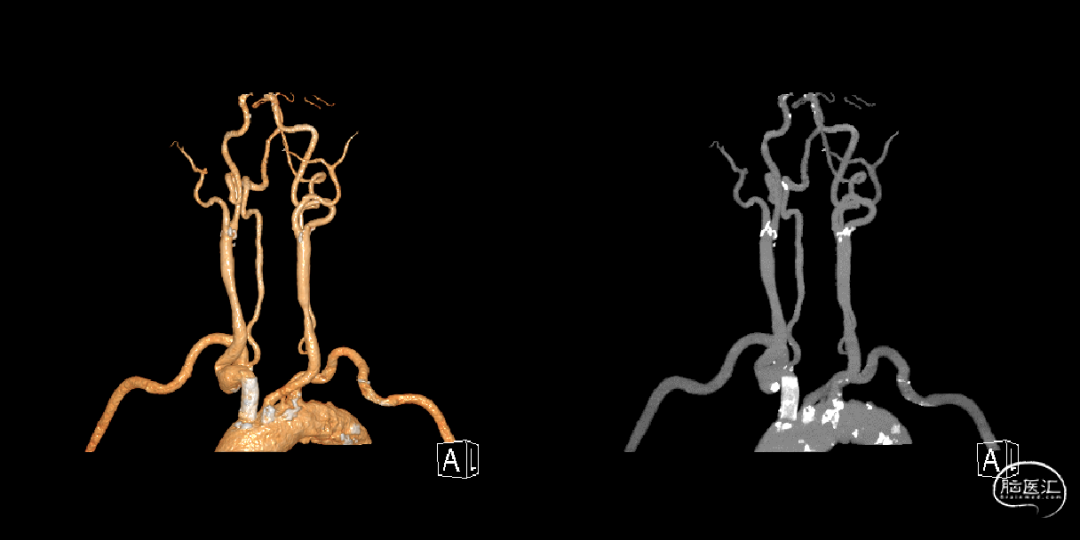

术后三日复查CTA如下,复查CT可见支架位置及形态良好,支架内及远端血流良好。

术后三天CTA